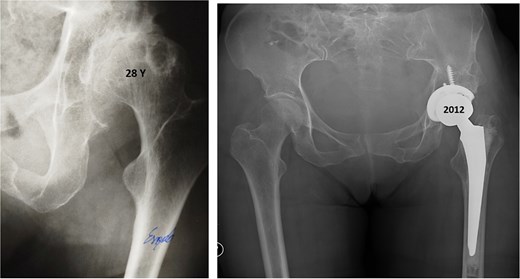

Thirteen years after THA, the 76-year-old patient continued to have a stable asymptomatic hip. Hip radiographs showed unchanged and stable positioning of the acetabular cup and femoral stem, with no measurable subsidence or radiolucent lines around the components (Fig. 4).

Postoperative anteroposterior radiographs of the pelvis 13 years after the THA, showing mechanical stability of the prosthesis with no evidence of loosening. No signs of osteoarthritis are present in the right hip (Tönnis Grade 0).